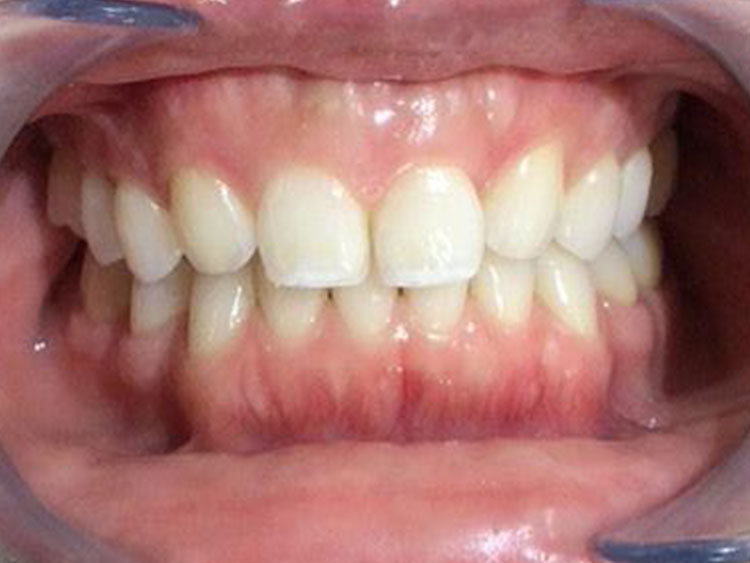

AFTER

50代。 「噛んだ時に違和感がある」「疲れると歯茎が浮くような感じがする」とのことでご来院。 レントゲン撮影の結果、過去に治療した歯の根の先に細菌が繁殖し、大きな炎症(黒い影)ができている「根尖性歯周炎」の状態でした。